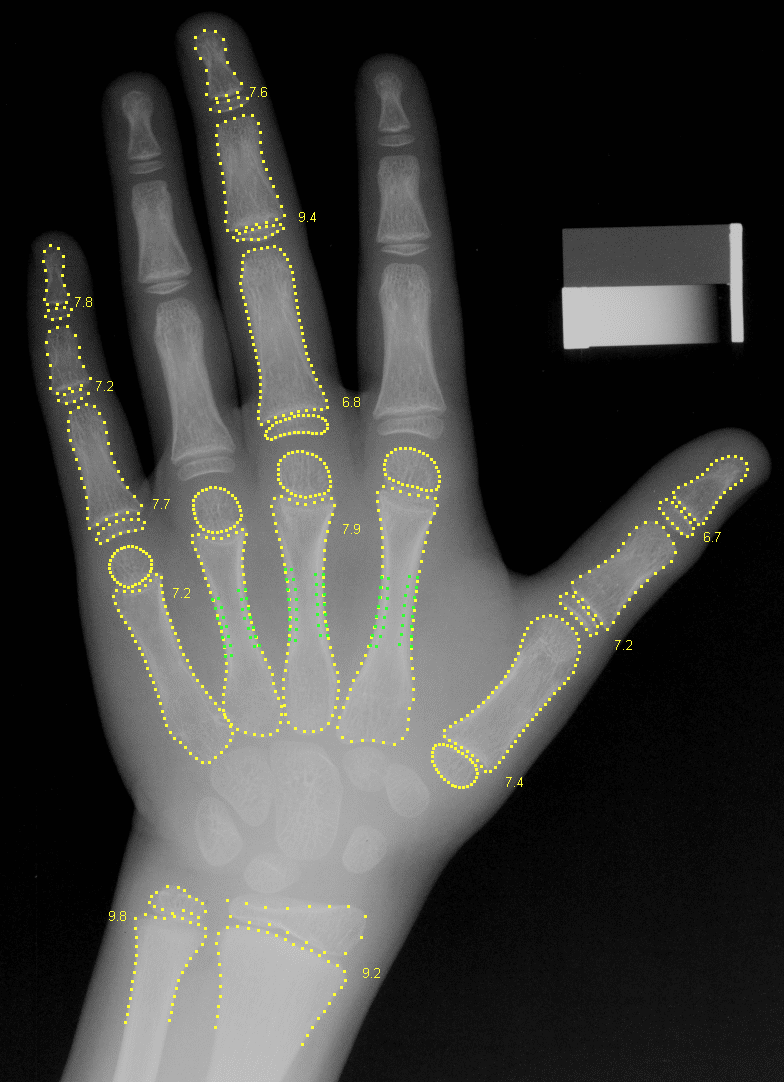

[1] Thodberg HH, Kreiborg S, Juul A, Pedersen KD: The BoneXpert Method for Automated Determination of Skeletal Maturity, IEEE Trans Medical Imaging, Vol. 28 (1), pp 52-66 (2009), abstract. (A pdf for personal use can be obtained by sending an email to )

[2] van Rijn R, Lequin MH, Thodberg HH: Automatic Determination of Greulich and Pyle bone age in healthy Dutch children, Pediatric Radiology Vol. 39 (6) pp 591-7 (2009), pdf (open access), Figure 1 in good quality